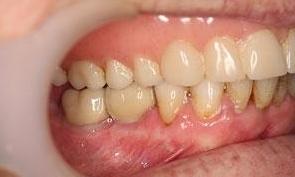

This before and after showcases a comprehensive dental restoration involving root canal therapy, the placement of dental crowns for structural integrity and aesthetics, as well as a full upper denture to restore function and appearance.